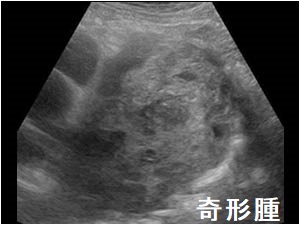

奇形腫

手塚治虫のブラックジャックで有名な奇形腫。内部に歯・皮脂などを含み、エコーで内部不均一に見えます。むしろCTの方が、内部の成分を明瞭に鑑別できます。